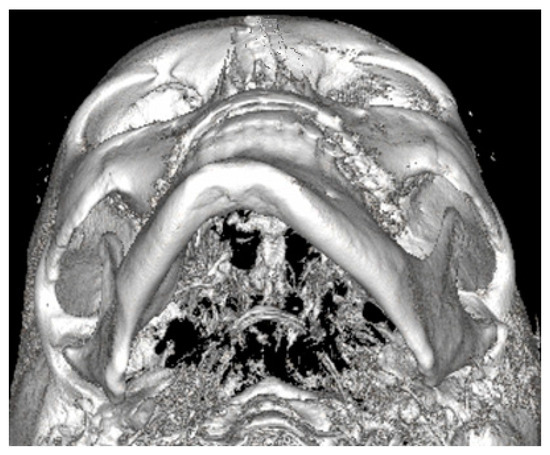

Figure 3.

LDCT—evaluation in low-dose CT focused on central symmetry line and differences in measurements between mental foramina, MIB, chin position, and mandibular angle contour.

3.4. Low-Dose Computer Tomography

Both panoramic radiographs and LDCT evaluations are important for any surgery planning. There is a possibility to estimate the shape and position of the mandibular canal while tracing its course on 3D evaluation and then estimating the degree of surgery in MIB (Figure 3 and Figure 4). Secondly, based on the studied patients’ data, the authors also include that the position of the mental foramina, chin deviation, and Go reference points described herein are valuable reference points for future surgical planning. Another important feature possible to estimate on 3D-LDCT is the scope of mandibular basis overgrowth in three dimensions.